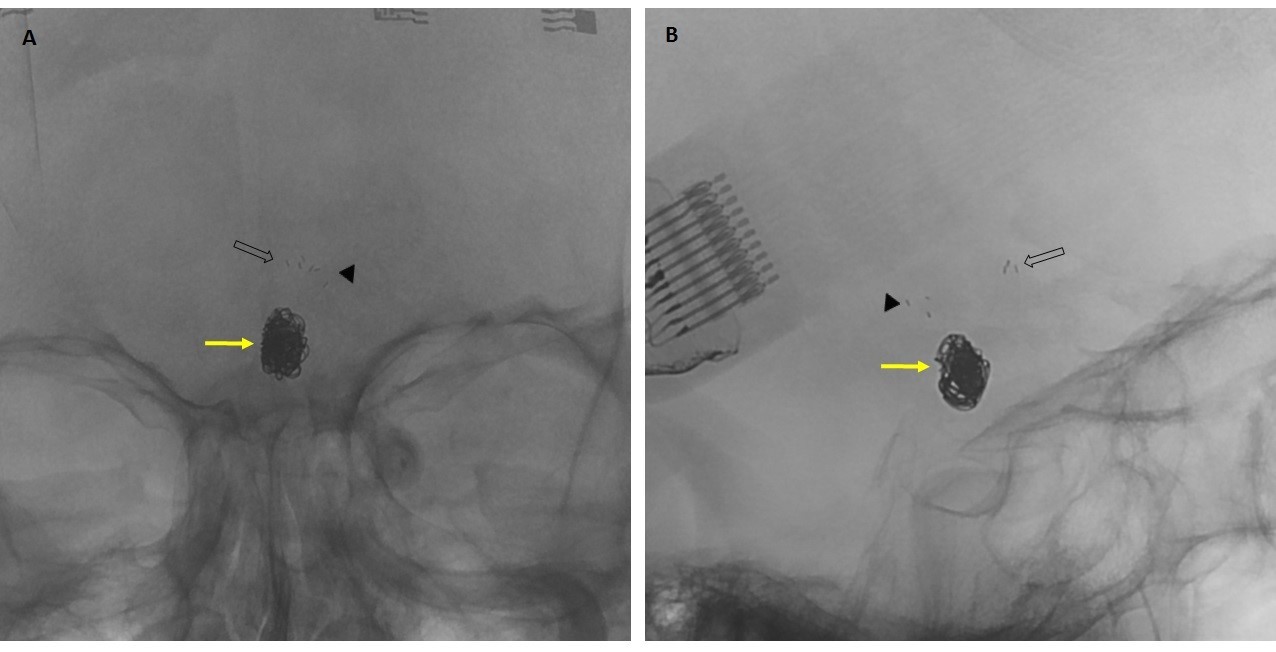

Imagen 2: Series angiográficas (Ay B) y reconstrucciones 3D de adquisición rotacional (C y D) que muestran aneurisma sacular de arteria comunicante anterior (flecha amarilla) y sus medidas. Asocia ausencia de segmento A1 derecho.

Se obtienen series angiográficas en proyecciones anteroposterior y lateral de cráneo y adquisición rotacional con reconstrucción 3D que confirman la presencia de un aneurisma sacular de arteria comunicante anterior, de aproximadamente 3mm de cuello por 6mm de diámetro máximo y 8 mm de fondo, en dirección anterocaudal, coexistiendo aplasia del segmento A1 de la arteria cerebral anterior (ACA) derecha por lo que el flujo de ambas AACCAA depende del eje carotídeo izquierdo (imagen 2).